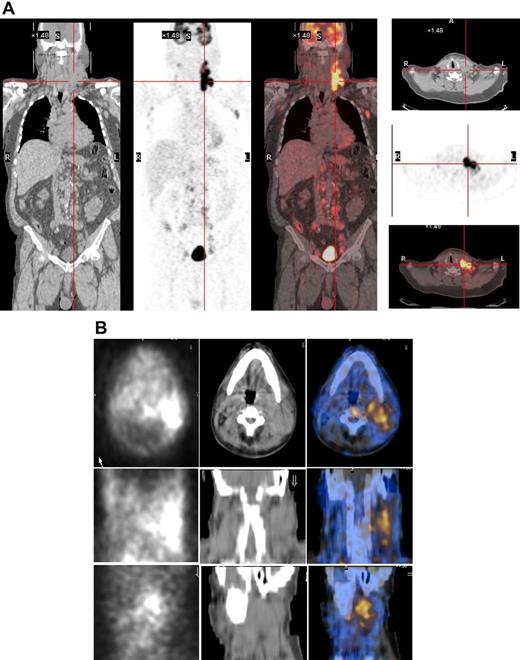

As the radiopharmaceutical 131I-L19SIP contains the very same binding moiety, L19, used for immunohistochemical determination of ED-B FN in lymphoma samples, this radiolabeled agent maintains both high affinity for the target antigen and binding properties typical to other L19 fusion proteins.35 In the patient with advanced SLL NHL, transaxial, coronal, and sagittal 131I-L19SIP SPECT-CT images demonstrated selective ED-B FN targeting in a palpable, enlarged lymph node conglomerate in the left cervical region, which corresponded to high 18F-FDG uptake on the baseline PET-CT scan (Figure 5). The absorbed dose in the target lesion was estimated at approximately 18 Gy, whereas it was 0.99 Gy and 0.42 Gy in the bone marrow and kidney, respectively. The patient was subsequently treated with a dose of 5.55 GBq 131I-L19SIP. He achieved disease stabilization at 1 month after therapy with the sum of involved lymph node diameters unchanged from baseline (403 vs 417 mm; baseline to 1 month after treatment). However, this patient experienced no clinical benefit from 131I-L19SIP radioimmunotherapy and went off study to receive palliative treatment.

131I-L19SIP uptake in lymphoma lesions in a patient (NHL1) with SLL NHL. (A) 18F-FDG PET scans demonstrate intense glucose metabolism in multiple enlarged lymph nodes, particularly in the left latero-cervical region. Coronal images are shown in the left panels and transaxial images of the cervical regions are displayed in the right panels. (B) The same patient received an intravenous infusion of 185 MBq and, subsequently, 5.55 GBq 131I-L19SIP. Transaxial, coronal, and sagittal SPECT-CT images of the cervical regions (first, second, and third rows, respectively) were acquired 8 days after the dose of 5.55 GBq. Left column shows scintigraphic images; central column, CT images; and right column, CT-scintigraphy fused images.